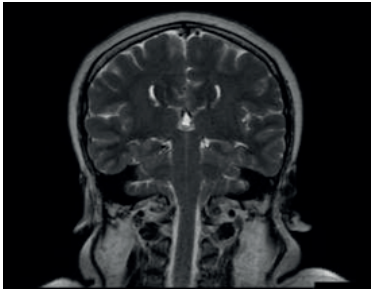

Paciente de sexo femenino, 37 años, derivada desde la policlínica de fertilidad. A los 11 años, en el contexto de evaluación por talla baja (debajo de 2 desvíos estándar (DE) de la media para edad y sexo), con hipocrecimiento (velocidad de crecimiento menor a -1 DE por más de un año, acompañado de talla baja) y retraso del desarrollo puberal, se diagnosticó hipogonadismo hipogonadotrófico y déficit de GH. Como etiología, presenta síndrome de De Morsier diagnosticado por resonancia nuclear magnética (RNM) a la misma edad que evidenció ausencia de septum pellucidum, hipoplasia del nervio óptico con hipoplasia de cuerpo calloso, tallo hipofisario y quiasma óptico traccionados ocupando la silla turca. Además, no se reconoce la neurohipófisis (figuras 1,2 y3).

La clínica es muy variada. Pueden ocurrir alteraciones visuales, neurológicas y endócrinas. Las alteraciones visuales ocurren secundariamente a la hipoplasia del nervio óptico, que van desde un daño parcial en la visión hasta ceguera, también se asocia a estrabismo y nistagmo. Esta paciente presentó desprendimiento de retina congénito en ojo derecho y nistagmo ocular bilateral. Las secuelas neurológicas comprenden retraso en el desarrollo cognitivo, convulsiones, hasta incluso parálisis cerebral. Cuando se tiene al menos una sospecha de SOD, que en esta paciente se evidenció por el fenotipo al nacimiento, labio leporino, trastorno ocular y nistagmo, se debe solicitar una RNM para evaluar anormalidades del hipotálamo-hipófisis y posibles defectos de la línea media5. Para el diagnóstico, deben estar presentes dos de tres criterios: ausencia del septum pellucidum, disgenesia del cuerpo calloso e hipoplasia del nervio óptico. Otros hallazgos posibles son microftalmia o anoftalmia, coloboma, hipófisis ectópica o hipoplasia, tallo hipofisario hipoplásico7. Los ejes hipofisarios más frecuentemente afectados son el somatotropo, corticotropo, tirotropo y déficit de hormona antidiurética (ADH). Esta paciente se presentó con un déficit de GH y un hipogonadismo hipogonadotrófico. En un estudio realizado en Estados Unidos, en 1984, observaron que de una muestra de 16 pacientes con SOD en un seguimiento de 3,5 años. El orden y grado de afectación de los ejes hormonales era similar a lo reportado en la literatura hasta el momento. Encontraron que 73% presentaba déficit GH aislada, y 34% de deficiencia de ACTH. Le siguen el déficit de hormona tirotropa (TSH) y ADH en 24% y 21%, respectivamente8. Se concluye que los déficits hormonales son frecuentes y pueden progresar en el tiempo, por lo que la evaluación endocrinológica regular es necesaria para la correcta sustitución y prevención de comorbilidades asociadas al hipopituitarismo.